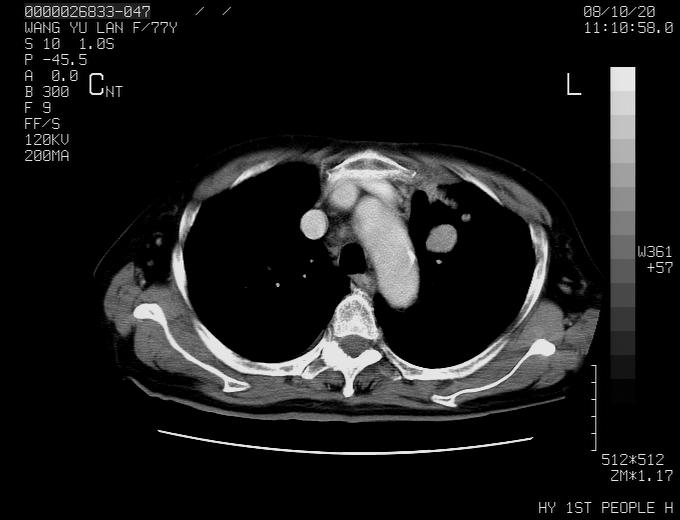

女性,77岁,胸部疼痛半月。左上肺团块影,本人考虑血管畸形,请分析

左上叶前段多发结节肿块并前段支气管息肉样结节、上叶腋亚段阻塞性肺炎,以结核可能性大。

纵隔有多个淋巴结肿大,提示周围型肺癌并转移可能性大。

动脉期未见大血管同步强化,首先考虑周围型肺癌

动脉期病灶近中线侧可见星芒状与大血管同等强化密度,支持考虑血管畸形伴血栓形成,动脉期不曲型,不除外周围型肺癌